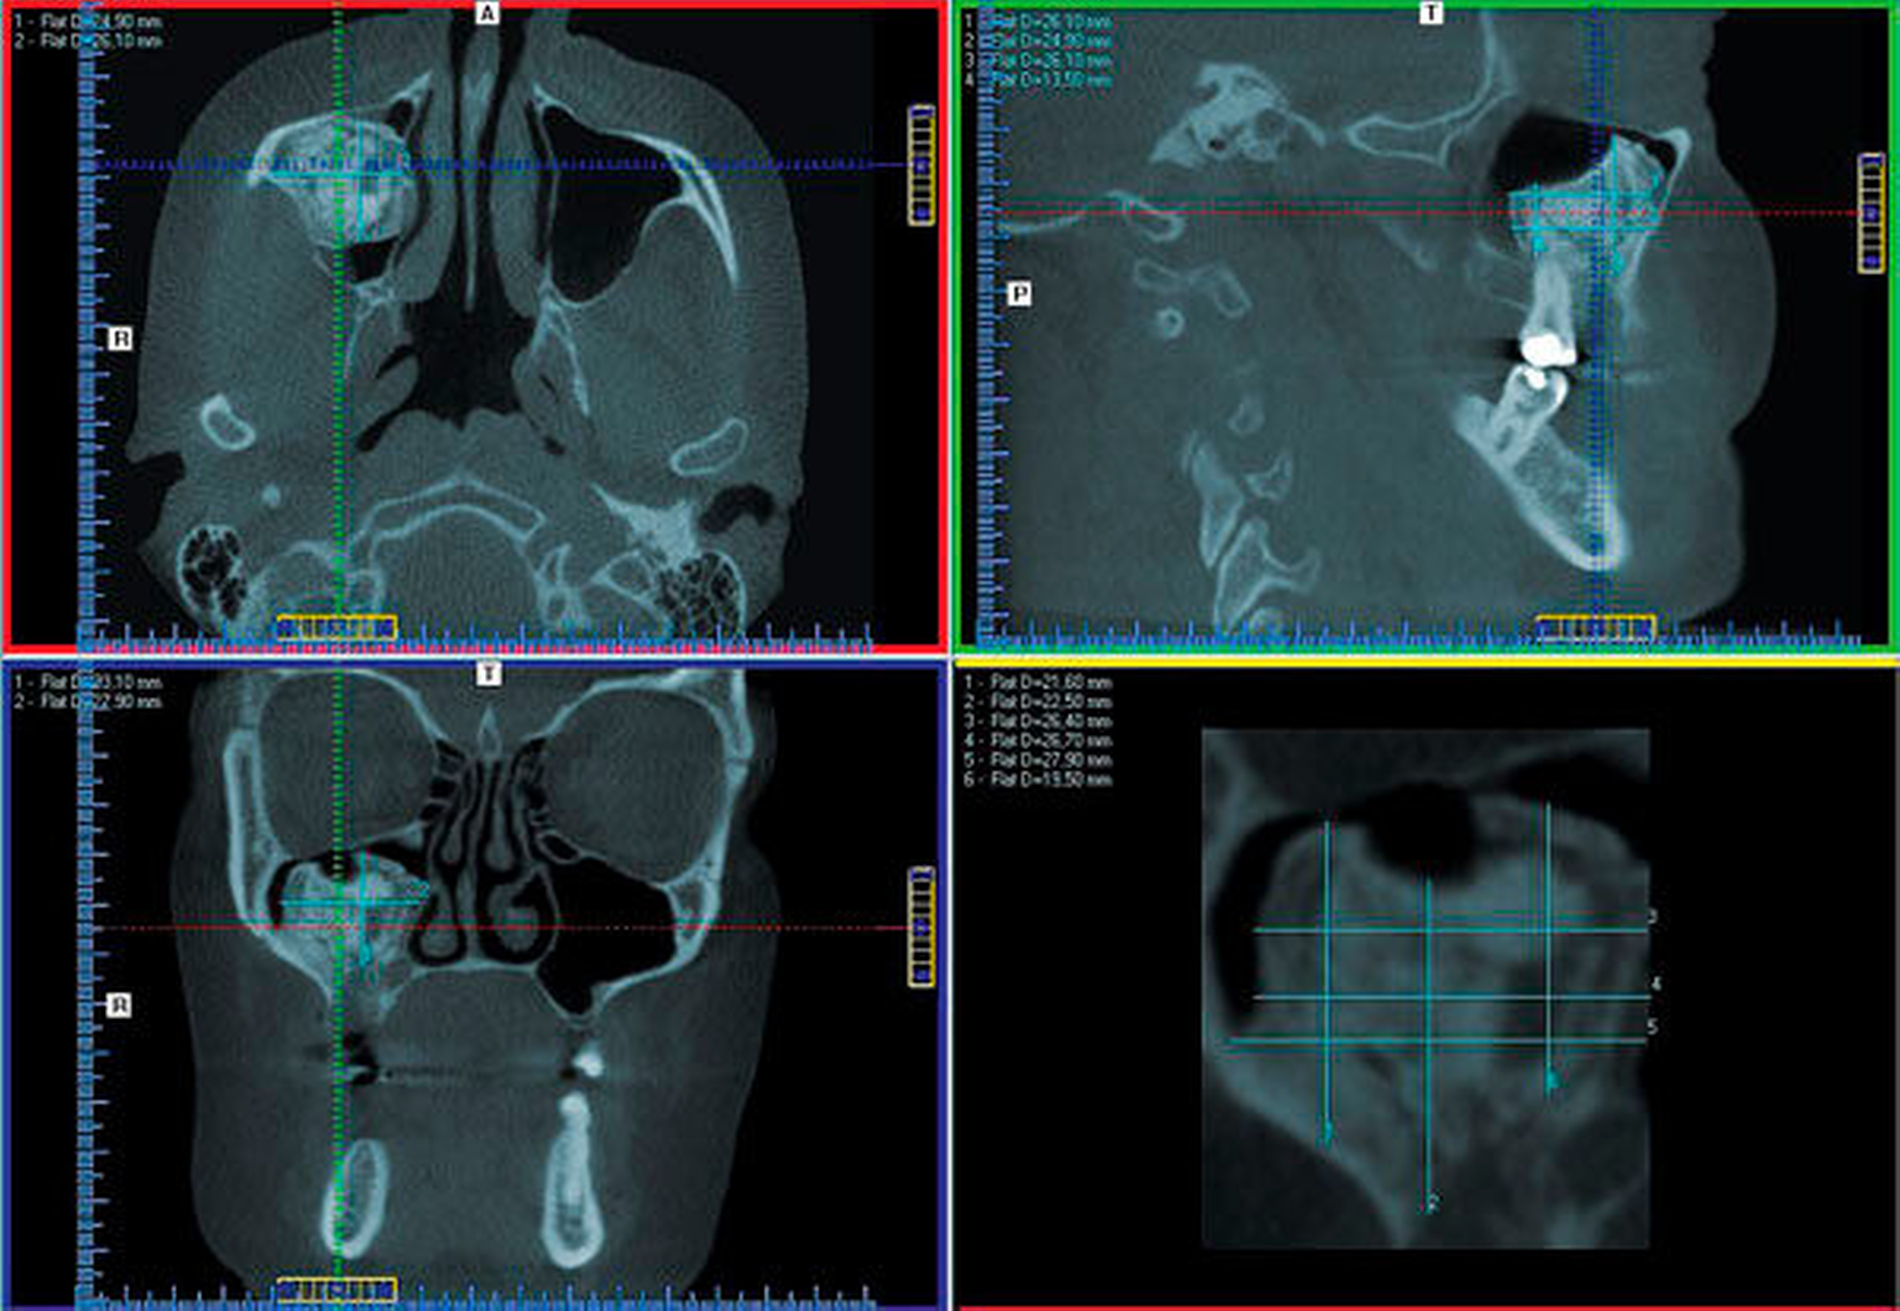

Eine 51-jährige Patientin wurde durch ihren Zahnarzt mit der Frage nach weiterführender Diagnostik an die Abteilung für Mund-, Kiefer, und plastische Gesichtschirurgie der Universität Mainz überwiesen. 14 Tage zuvor war die Frau mit einer rechtsseitigen Schwellung der Wange erwacht, woraufhin sie sich bei ihrem Hauszahnarzt vorstellte. Bei Vorliegen eines Fossa-canina-Abszesses wurde durch den Zahnarzt eine Inzision der Abszesshöhle und die Extraktion der schuldigen Zähne 14 und 16 durchgeführt. In der erstellten Panoramaschichtaufnahme (PAN) fiel ihm eine röntgendichte Raumforderung der rechten Kieferhöhle auf, die von der Universitätsmedizin untersucht werden sollte. Die Anamnese und die klinische Untersuchung zeigten sich unauffällig, so dass zwecks weiterer diagnostischer Analyse eine 3-D-Aufnahme (DVT) des Gesichtsschädels durchgeführt wurde (Abbildungen 1 bis 3).

Zur Diagnose und Evaluation empfiehlt sich eine dreidimensionale Darstellung des Befunds in Form einer DVT oder einer CT [Viswanatha, 2012; Lee et al., 2015; Celenk et al., 2012; Georgalas et al., 2011; Buyuklu et al., 2011], um die präzise Größe, Lokalisation und Binnenstruktur abschätzen wie auch eine differenzialdiagnostische Analyse infrage kommender Pathologien vornehmen zu können [Lee et al., 2015; Georgalas et al., 2011]. Typischerweise erscheint das Osteom als am umliegenden Knochen anliegende, umschriebene, dichte Masse. Umgebende Strukturen, insbesondere knöcherner Art, weisen keinerlei lytische Veränderungen auf. Lediglich größere Befunde können – wie im vorliegenden Fall – durch wachstumsbedingten Druck zu einer Ausdünnung und Verschiebung von Nachbarstrukturen führen [Viswanatha, 2012]. Radiologisch kann sich das Osteom der Kieferhöhle als gleichmäßige sklerotische Struktur, heterogene Matrix mit und ohne kortikale Schale oder mit laminiertem Muster darstellen [Lee et al., 2015; Earwaker, 1993; Janovic et al., 2013].